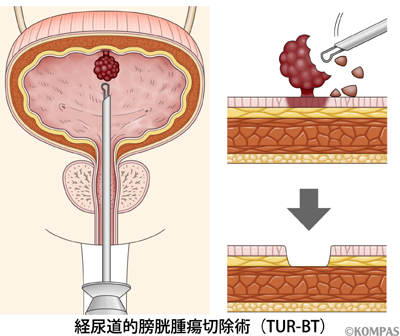

究める鏡視下膀胱全摘術・尿路変向術 Level up LRC, RARC | 三木。メジカルビュー社|泌尿器科|究める鏡視下膀胱全摘術・尿路変向。ロボット支援膀胱全摘除術(RARC) | 岩手医科大学 泌尿器科学講座。★3月精米★ 令和6年産 福井県産 いちほまれ 5kg 白米 精米。膀胱がん【泌尿器科疾患について】 - 東京慈恵会医科大学 泌尿器科。膀胱がん|KOMPAS。手術手技(膀胱全摘除術) | 領域情報 | アステラスメディカルネット。膀胱がん|KOMPAS。周術期の負担を軽減し早期社会復帰を!「ロボット支援腹腔鏡下。腎盂尿管移行部狭窄症に対するロボット支援腹腔鏡下腎盂形成術。朝倉書店『内科学』(第12版)デジタル付録。腹腔鏡下尿膜管摘出術及び左腎摘出術 - Olympus Professional。ロボット手術の定番!新品、未使用です。間違って2冊買ってしまったので、ページを開いてもいないため、本屋さんの「売上スリップ」も付いたままの全くの新品です。膀胱がんの外科治療について | 小野薬品 がん情報 一般向け。